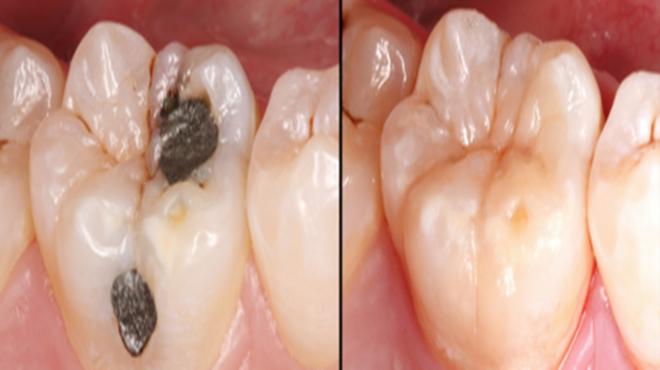

很多人因为常吃甜食或是过于刺激的食物,而没有及时刷牙,又或是晚上没有养成刷牙的好习惯,时间久了导致口腔内细菌的滋长,就可能诱发牙齿疾病。一般蛀牙就是这样生成的,牙齿表面出现黑色的小洞,若任其发展,小洞就会越来越大,吃饭塞牙,最终疼痛难忍。

蛀牙会带来疼痛,平时可能没啥感觉,但是只要一吃食物牙齿就会疼的厉害,久而久之就会造成偏嚼的习惯,让整个面部看起来都不协调,而且蛀牙如果发生在前牙,张口就是一个黑洞,那该多难看啊。